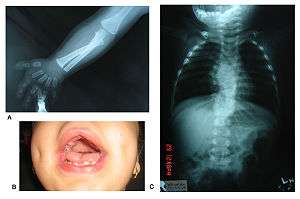

Note characteristic fetal face, hypogenitalism and brachydactyly of hands and feet.

X-ray upper limbs and hands showing mesomelic shortening and brachydactyly (A), gingival hyperplasia (B) and X-ray vertebrae showing hemivertebrae and vertebral fusion.

Patients suffer from dwarfism, short lower arms, small feet, and small hands. Fingers and toes may also be abnormally short and laterally or medially bent. The thumb may be displaced and some patients, notably in Turkey, experience ectrodactyly.[1] All patients often suffer from vertebral segmentation abnormalities. Those with the dominant variant have, at most, a single butterfly vertebra.[2] Those with the recessive form, however, may suffer from hemivertebrae, vertebral fusion, and rib anomalies. Some cases resemble Jarcho-Levin syndrome or spondylocostal dysostosis.